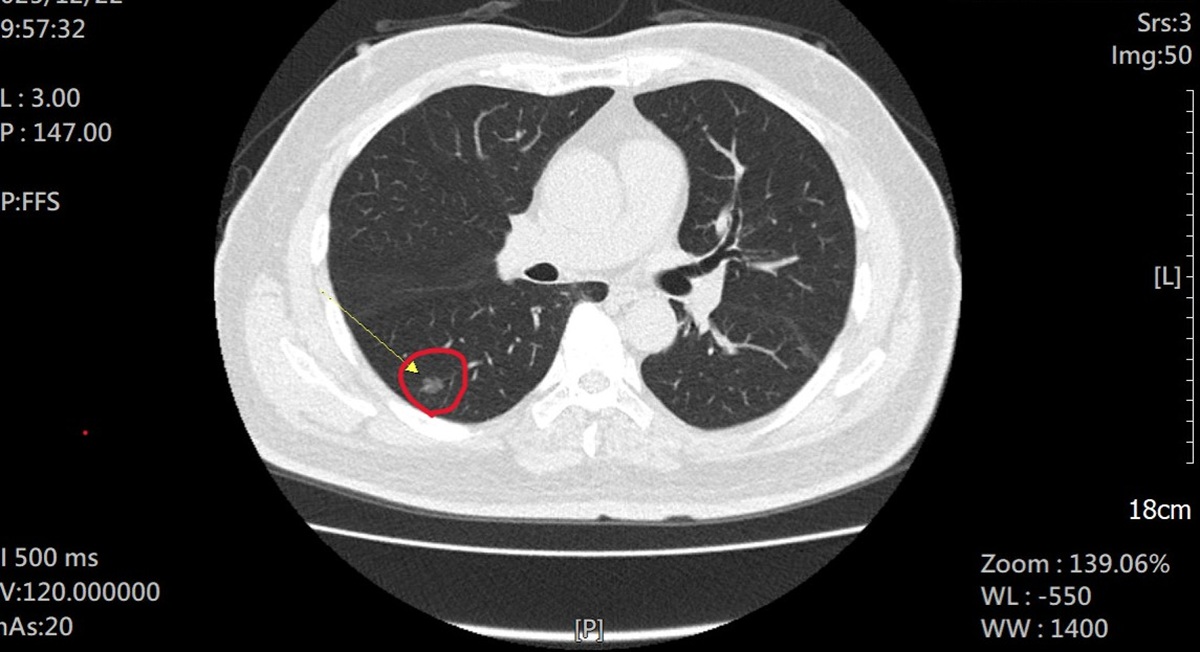

66歲陳姓男子抽菸30餘年,雖然家人一直勸他戒菸,但始終未能成功。去年年底第一個孫子誕生,他為小嬰兒不要吸二手菸,下定決心戒菸,前往員榮醫院胸腔內科主任林鴻慶醫師戒菸門診。因符合國健署肺癌補助計畫,接受「低劑量電腦斷層(LDCT)」篩檢。沒想意外揪出右下肺部有一處直徑約 1 公分的毛玻璃狀病變,疑似早期肺腺癌。

針對陳姓患者的影像報告,林主任與在員榮醫院駐診的秀傳醫院副院長胸腔外科李佳穎醫師評估後,建議立即手術切除。陳姓患者隨後在員榮醫院接受李佳穎副院長施作「單孔微創胸腔鏡手術」。此術式僅需一個微小切口,具有出血量少、術後疼痛度低等優勢,術後第 3 天即順利出院,病理檢驗證實為初期肺腺癌。讓陳姓患者感慨萬分,直呼除醫護專業照護外,小孫子更是他的「救命恩人」,讓他能在黃金期及早發現病灶。

▲林主任強調,LDCT 是目前唯一能有效偵測直徑 1 公分以下細微病灶的工具。(圖/員榮醫院提供)

林主任強調,LDCT 是目前唯一能有效偵測直徑 1 公分以下細微病灶的工具。臨床數據顯示,第一期肺癌的五年存活率高達 90% 以上;反之,一旦延誤至第四期,存活率則驟降至約 15%。早期發現比晚期發現,患者五年存活率差 6 倍。